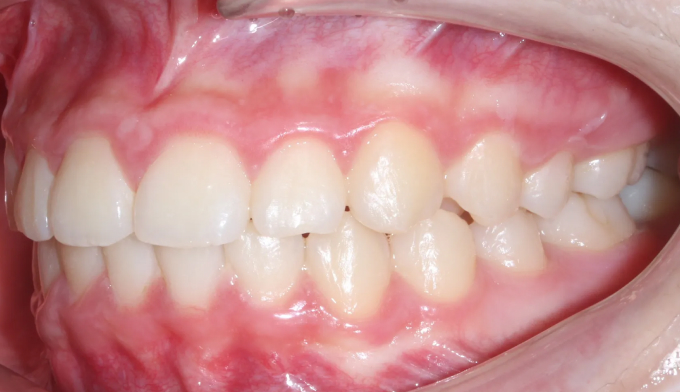

위 작은어금니가 겹쳐져서 맹출하였습니다.

공간이 부족하므로 먼저 양쪽으로 치아를 벌려 공간을 확보해준 후 겹쳐진 치아들을 배열해줍니다.

치아 배열 중 앞니가 뻐드러지지 않게 조심합니다.

총 치료기간은 20개월입니다.